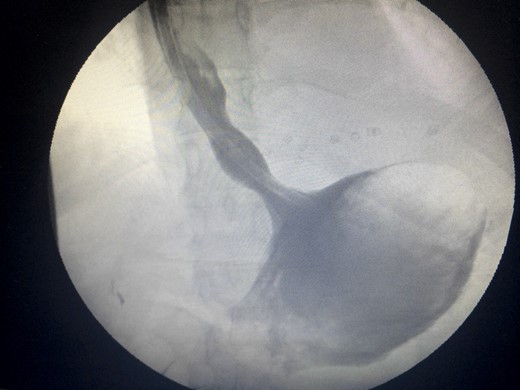

Two days prior to her admission, she had undergone upper gastrointestinal endoscopy for the same complaint in another center that revealed a dilated gastric lumen with herniation of the distal stomach, pylorus and first part of the duodenum into the left hemi-thorax (Fig. 2). She refused treatment and left against medical advice. She presented to our emergency department with worsening symptoms. Resuscitation was commenced with immediate nasogastric decompression, intravenous hydration and analgesia, proton-pump inhibitors and electrolyte replacement. A double contrast-enhanced computed tomography (CT) scan of the chest and the abdomen demonstrated a large diaphragmatic defect (7 × 7 cm) and a left diaphragmatic hernia containing a dilated stomach, suggestive of a gastric outlet obstruction (Fig. 3). A water-soluble gastrografin meal was performed, showing an intra-thoracic, mesentero-axial gastric volvulus (Fig. 4).

Water-soluble gastrografin meal showing an intra-thoracic mesentero-axial volvulus.